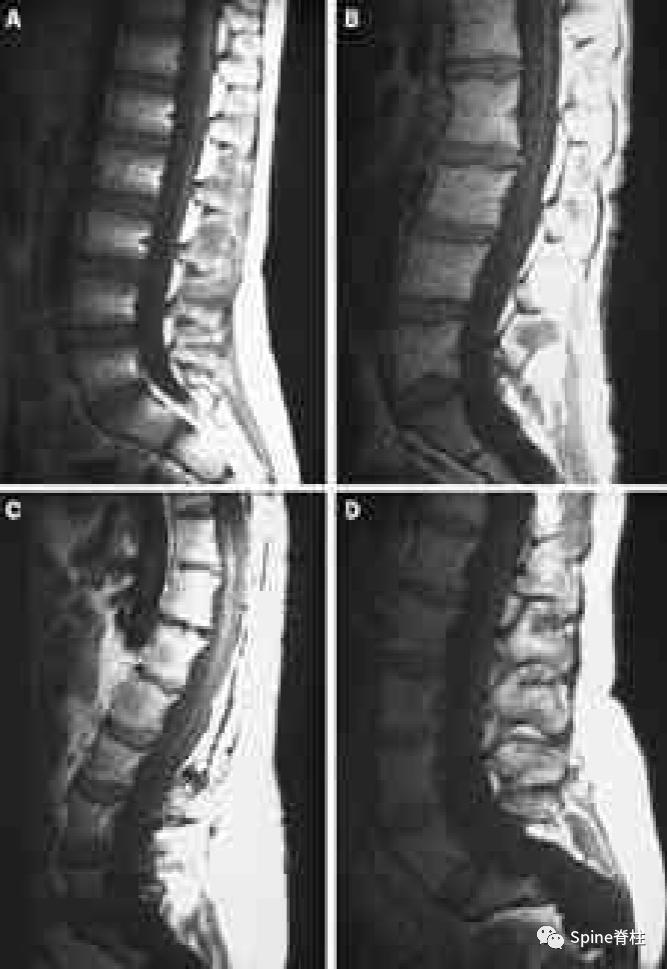

一名18岁男性因腰痛接受MRI检查,下图为矢状位T2(1a)和T1加权像(1b)、S1水平横断面T2(1c)和T1加权像(1d)。

在矢状位T2(2a)和T1加权像(2b)上,多节段椎体后壁呈扇形缺损,缺少硬膜外脂肪(红色箭头),S1处的硬膜囊直径大于L4处。横断面T2(2c)和T1加权像(2d)提示硬膜囊膨胀,S1椎体后壁再次证实硬膜外脂肪缺失(红色箭头)。 其影像学表现符合硬膜扩张的诊断

矢状位T2(a)和T1(b)加权像提示下胸椎和上腰椎硬膜扩张伴显著的椎体后壁扇形凹陷(红色箭头)。轴位T2(c)和T1(d)加权像提示硬膜囊外侧膨出(绿色箭头)伴椎体扇形缺损。蓝色箭头是指继发于皮肤神经纤维瘤的多发性皮肤结节